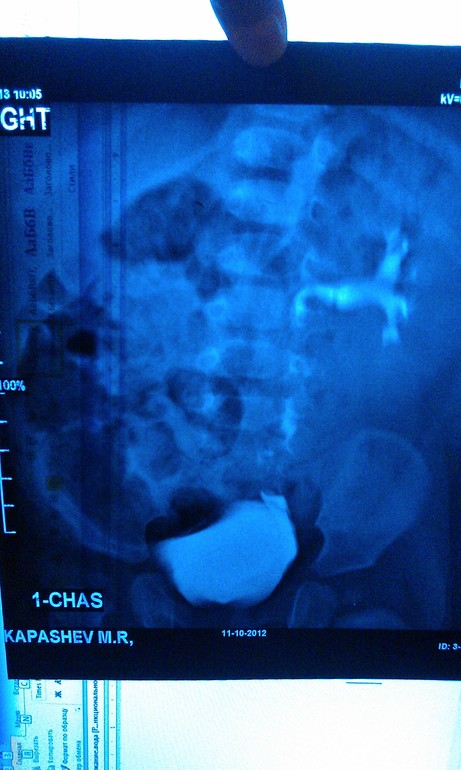

Урография

Максиим Викторович. Если возможно, могли бы вы прокомментировать нашу урограмму. Заключение рентгенологов и урологов разнятся. Хотелось бы послушать мнение третьего специалиста.

Олеся, я бы с радостью, но так снимки объективно оценить не смогу, тем более не зная клинической ситуации. Слева понятно, а с правой почкой что?